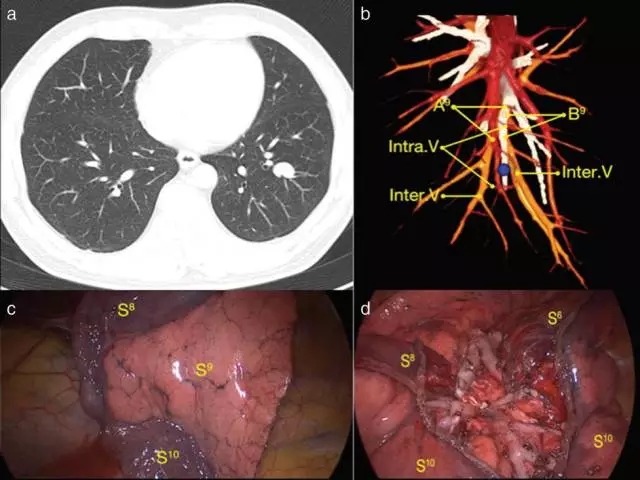

从2013年到2015年,539例结节小于2厘米的非小细胞肺癌病人,接受了全胸腔镜解剖性肺段切除术。术前采用3D-CTBA技术,辨别靶肺段支气管和动脉,以及段内静脉和段间静脉的分布, 明确手术的路径和切除的边界范围,见图a和b。

开刀侧的肺,予以充气张肺,气道压力控制在20厘米水柱,经过5-12分钟,靶段肺完全膨胀,然后改回对侧肺单肺通气,让手术侧的肺气道与大气相通,这时,就能非常清晰地看到“英得福线”,见图c,靶段肺膨胀,其周边正常肺段组织萎陷,产生清晰的分界线。沿“英得福线”和段间静脉分离,至肺野外周三分之一,用腔镜切割吻合器切断靶段与周边肺段间组织,这样可以完整切除“锥形”的靶段肺组织,见图d. 采用这种技术,“英得福线”和肺本身的肺段分界线完全吻合。